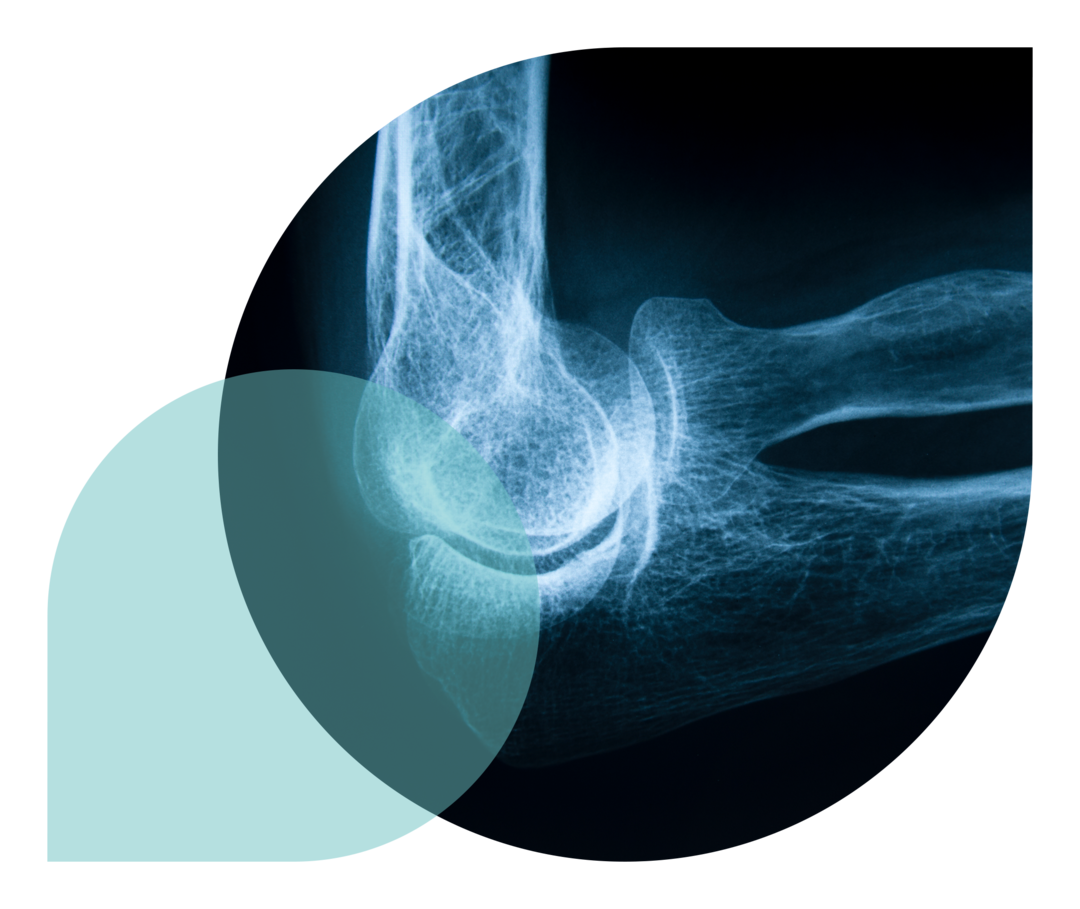

Für die Diagnose von rheumatoider Arthritis werden auch bildgebende Verfahren genutzt, um den Ist-Zustand der Gelenke zu erfassen. Ultraschall wird dabei vor allem verwendet, um Gelenkergüsse und Verdickungen der Sehnen zu identifizieren. Weitere bildgebende Verfahren, die zum Einsatz kommen, sind die Magnetresonanztomografie (MRT) und die Szintigrafie (nuklearmedizinische Untersuchung).